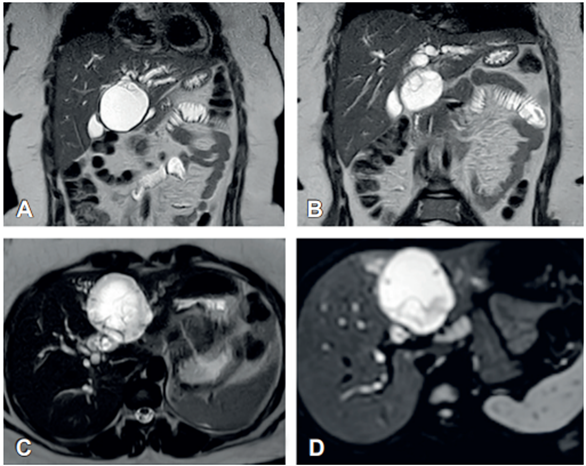

Inicialmente se realizó una ecografía de hígado y vías biliares, encontrando un quiste multiseptado en el segmento IVB de 63 x 60 mm, comunicado con la vía biliar izquierda; y dilatación de ambos conductos hepáticos. Dados los hallazgos se realizó una colangiorresonancia en la que se observó una lesión quística multiseptada de 63 x 60 mm en el segmento IVB del hígado, marcadamente hiperintensa en T2 (Figura 1), con componente exofítico, comunicada con la vía biliar intrahepática izquierda, con septos delgados que realzaban al medio de contraste y focos menores de 6 mm restringidos en la difusión tisular. La lesión comprimía el conducto hepático común, causando dilatación de la vía biliar intrahepática en ambos lóbulos.

Figura 1. A-B. Cortes coronales de colangiorresonancia en secuencia T2 donde se observa la imagen quística, resaltada en color blanco. C-D. Cortes axiales de la lesión donde se aprecia la difusión tisular restringida.

Mujer de 35 años, residente en área urbana, nulípara, con antecedente poco claro de colectomía derecha en el 2020 por endometriosis, sin otros antecedentes de importancia. Durante el seguimiento de su enfermedad ginecológica se realizó una resonancia magnética contrastada de abdomen donde se observó una lesión quística en los segmentos II y III del hígado de 10 x 7 x 8 cm, con septos gruesos (Figura 5). Debido a este hallazgo en una paciente asintomática, se decidió programar una hepatectomía por laparoscopia de dichos segmentos.

Figura 5. A-B. Cortes coronales. C-D. Cortes axiales de la colangioresonancia en secuencia T2, donde se puede ver la lesión.